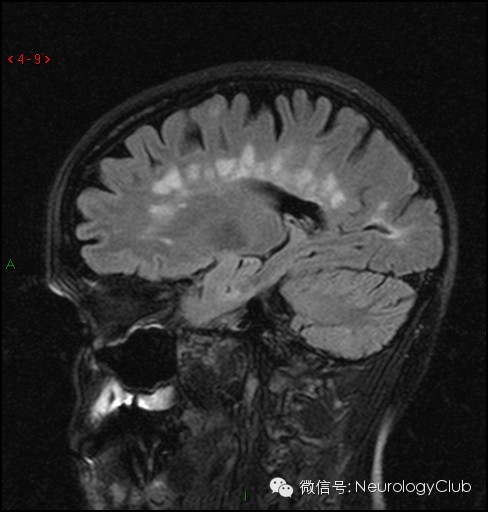

第三方面:胼胝体病变

1T2矢状位观察

2、特征:病灶以带毛缘的形态自胼胝体向外延伸,“虫蚀样”或称道森指征(Dawson’s finger sign)

3、可与脑血管病等鉴别